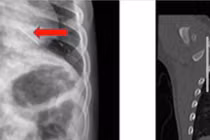

Ho ra máu đỏ tươi, không ngờ trẻ 3 tuổi nuốt đoạn kẽm nhung dài 2cm

Bệnh viện Nhi đồng TP HCM cấp cứu trẻ bị hóc dị vật kẽm nhung dài 2cm, cảnh báo nguy hiểm và nhấn mạnh phòng tránh dị vật cho trẻ nhỏ.